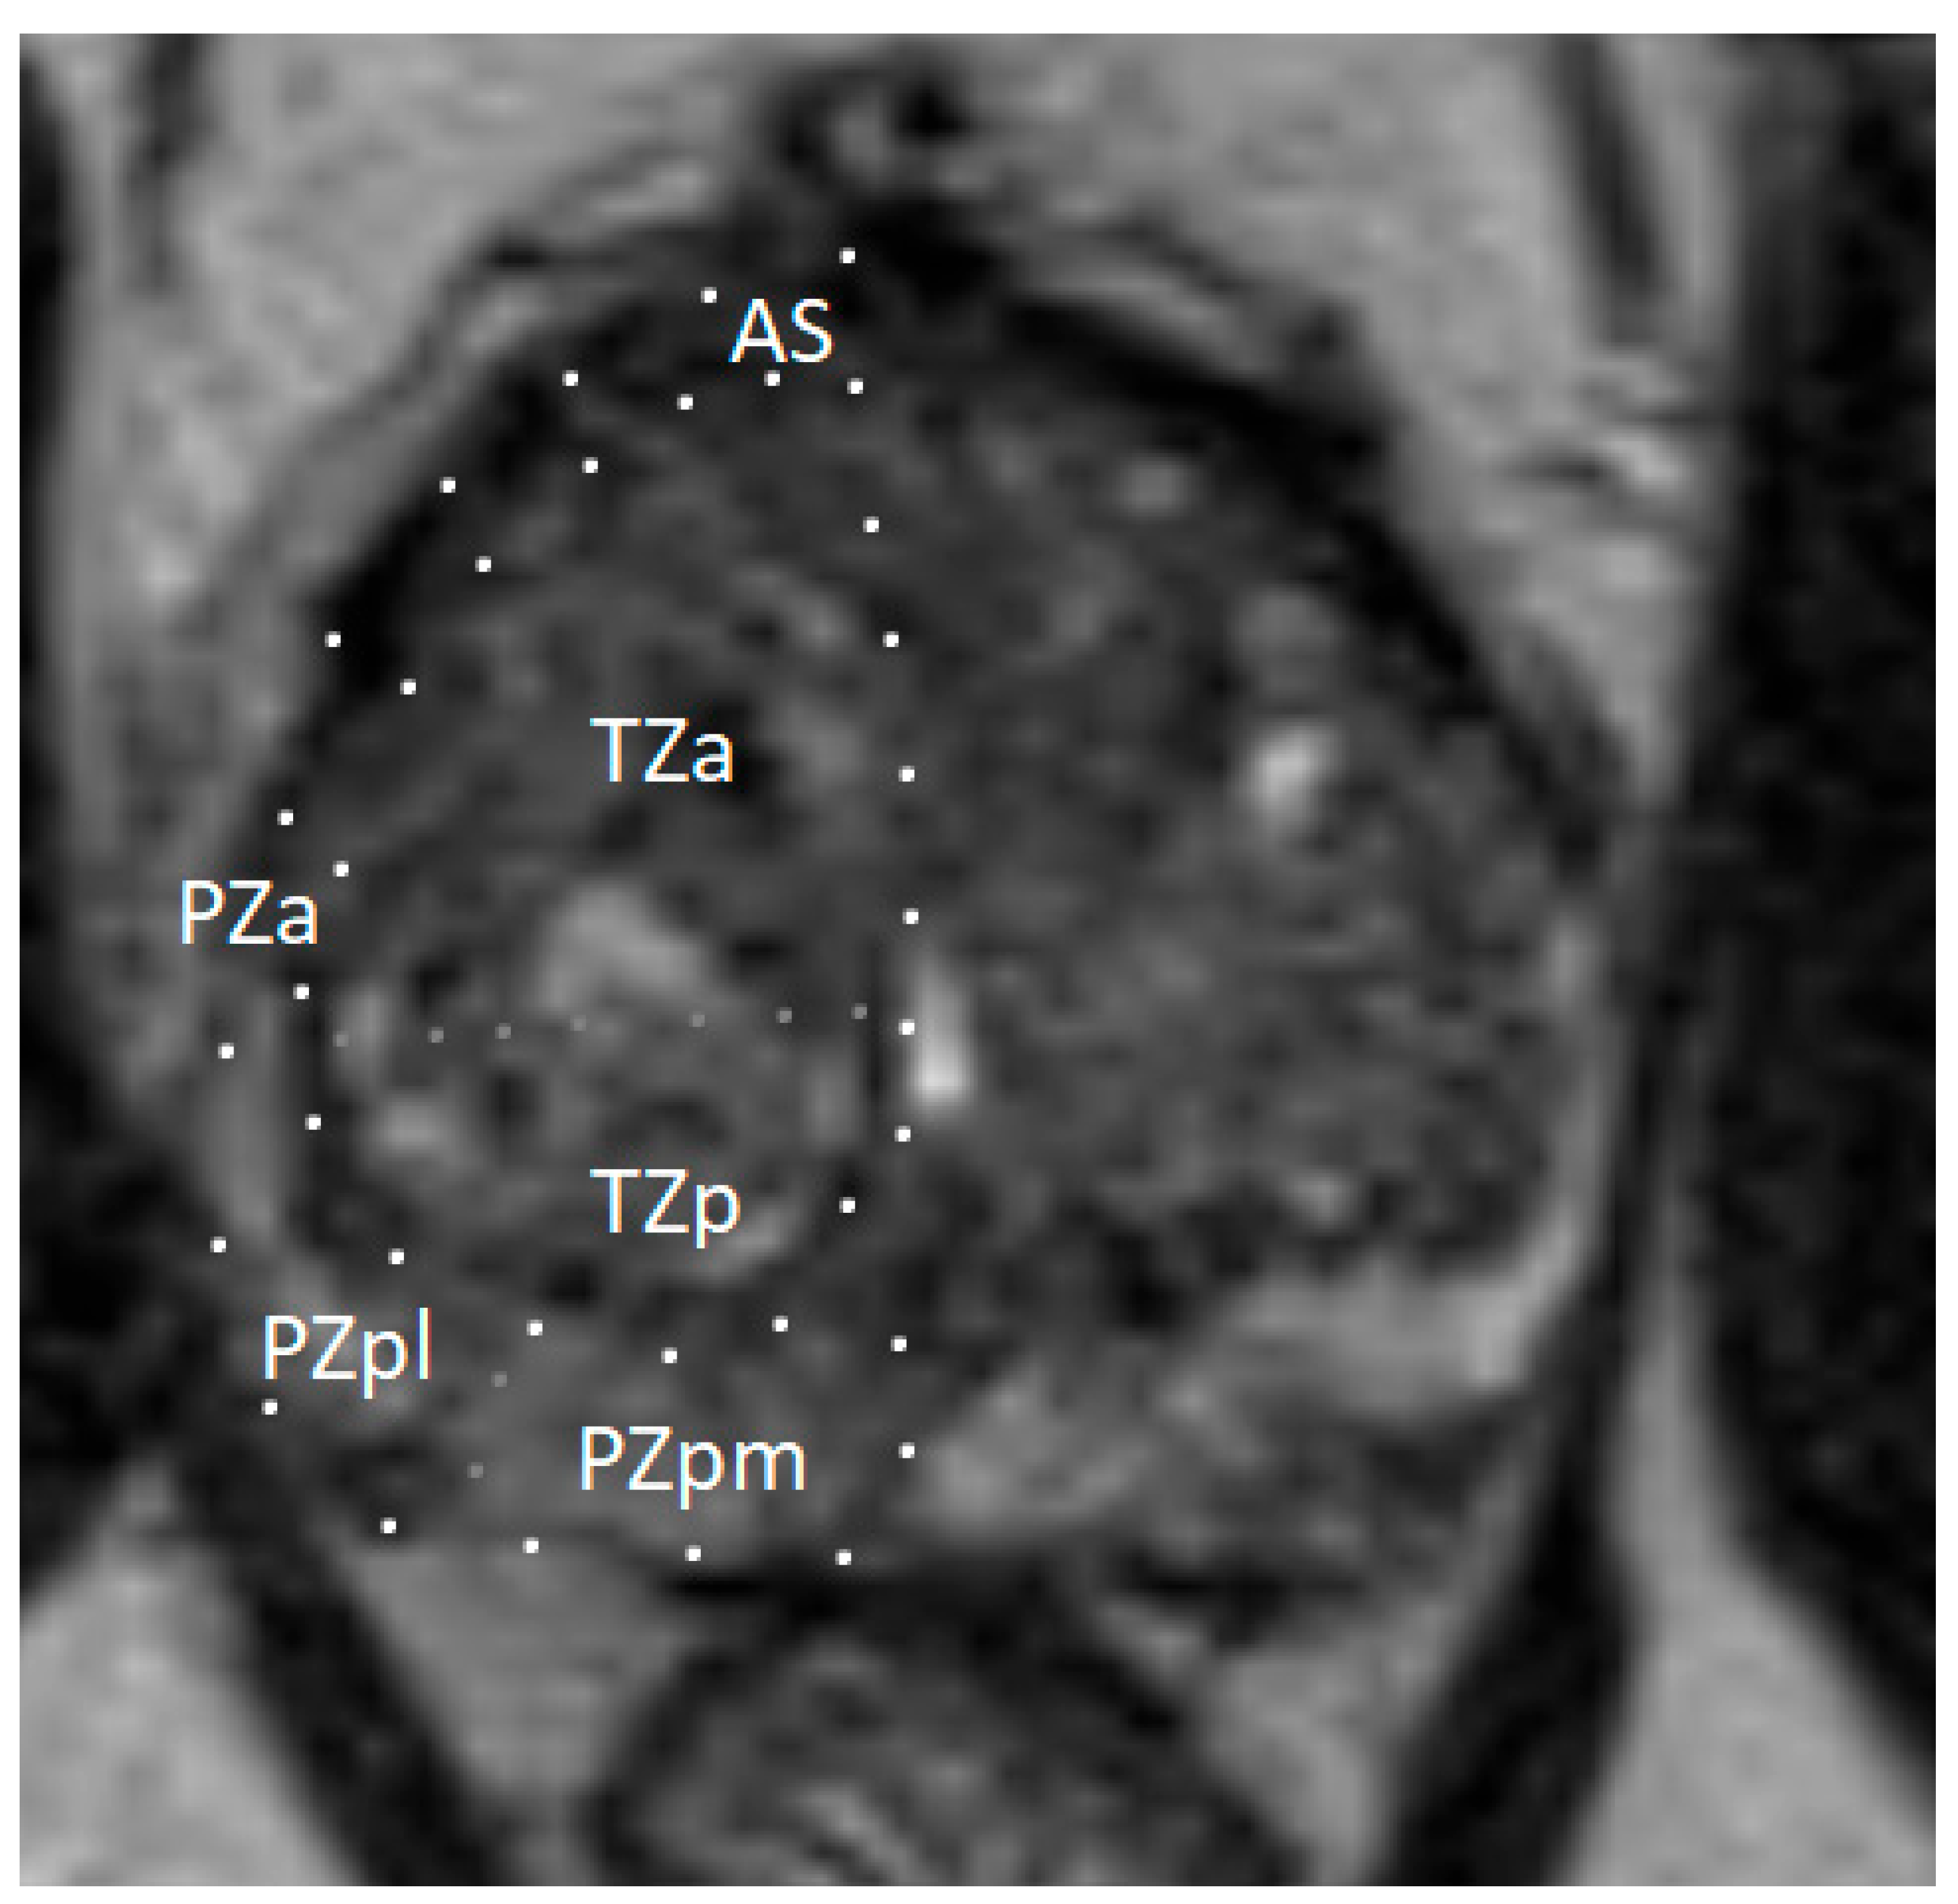

The prostate gland is a small, walnut-sized exocrine organ. It is located in the lesser pelvis, between the bladder and the urogenital diaphragm, near the external urethral sphincter. The prostate consists of fibromuscular stroma and glandular elements, with excretory ducts lined by epithelial cells. The gland surrounds the proximal portion of the urethra, called the prostatic urethra, which measures approximately 4 cm in length. The vasa deferentia enter the prostate posteriorly, joining the urethra at the level of the ejaculatory ducts. Anatomically, the prostate consists of two lateral lobes and, in some individuals, a prominent median lobe [5]. The prostate is divided into peripheral, transition, and central zones—key anatomical regions for imaging-based lesion localization (see Figure 1). Approximately 80% of PCa cases originate in the peripheral zone, while 20–25% arise from the transition zone. Cancers in the central zone are uncommon and are usually extensions of tumors originating in the transition zone [6].

Figure 1.

Zonal anatomy of the prostate gland on axial multiparametric magnetic resonance imaging (mpMRI). Adapted from the authors’ own materials, based on Yacoub and Oto [7]. a: anterior; AS: anterior [fibromuscular] stroma; p: posterior; pl: posterior lateral; pm: posterior medial; PZ: peripheral zone; TZ: transition zone.